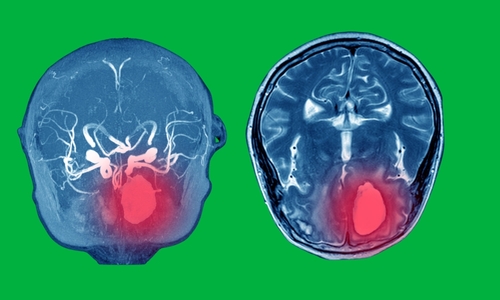

Συνίσταται μια πλήρης κλινική εξέταση η οποία θα περιλαμβάνει λήψη όλων των απαραίτητων πληροφοριών που αφορούν την παθολογία, αλλά και εξειδικευμένες απεικονιστικές εξετάσεις όπως ακτινογραφία θώρακος, ηλεκτροκαρδιογράφημα (ΗΚΓ), υπερηχογράφημα καρδιάς, διοισοφάγειο υπερηχογράφημα καρδιάς (ΤΕΕ), μαγνητική τομογραφία (MRI) και αξονική τομογραφία (CT).

Σύσταση για χειρουργική επέμβαση απαιτείται βάση των ευρημάτων – εάν το μέγεθος/εύρος της αορτής είναι μη φυσιολογικό σε σχέση με την ηλικία, το ύψος, το φύλο και τις διεθνείς κατευθυντήριες οδηγίες.